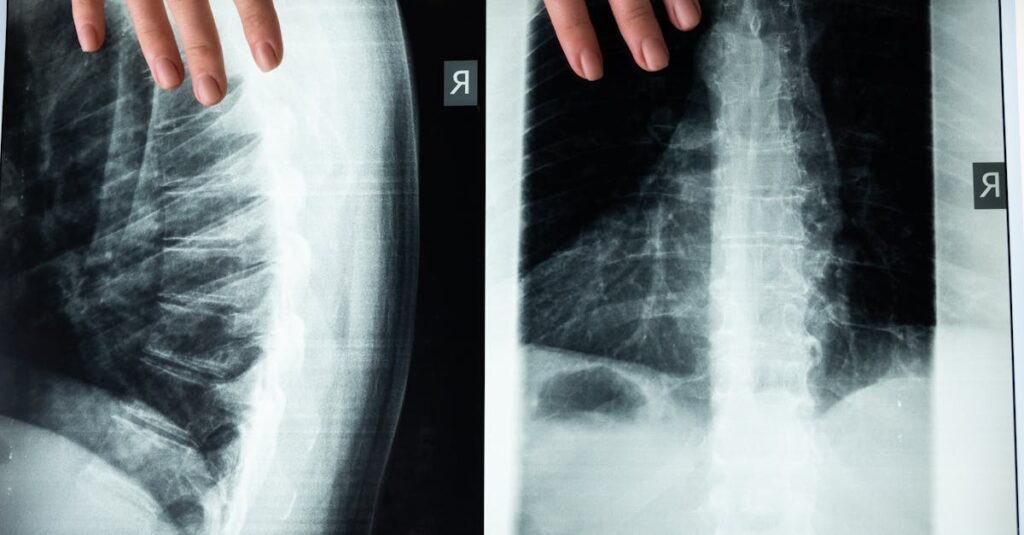

Une IRM ou une radiographie est souvent nécessaire pour évaluer l’état de la colonne vertébrale.